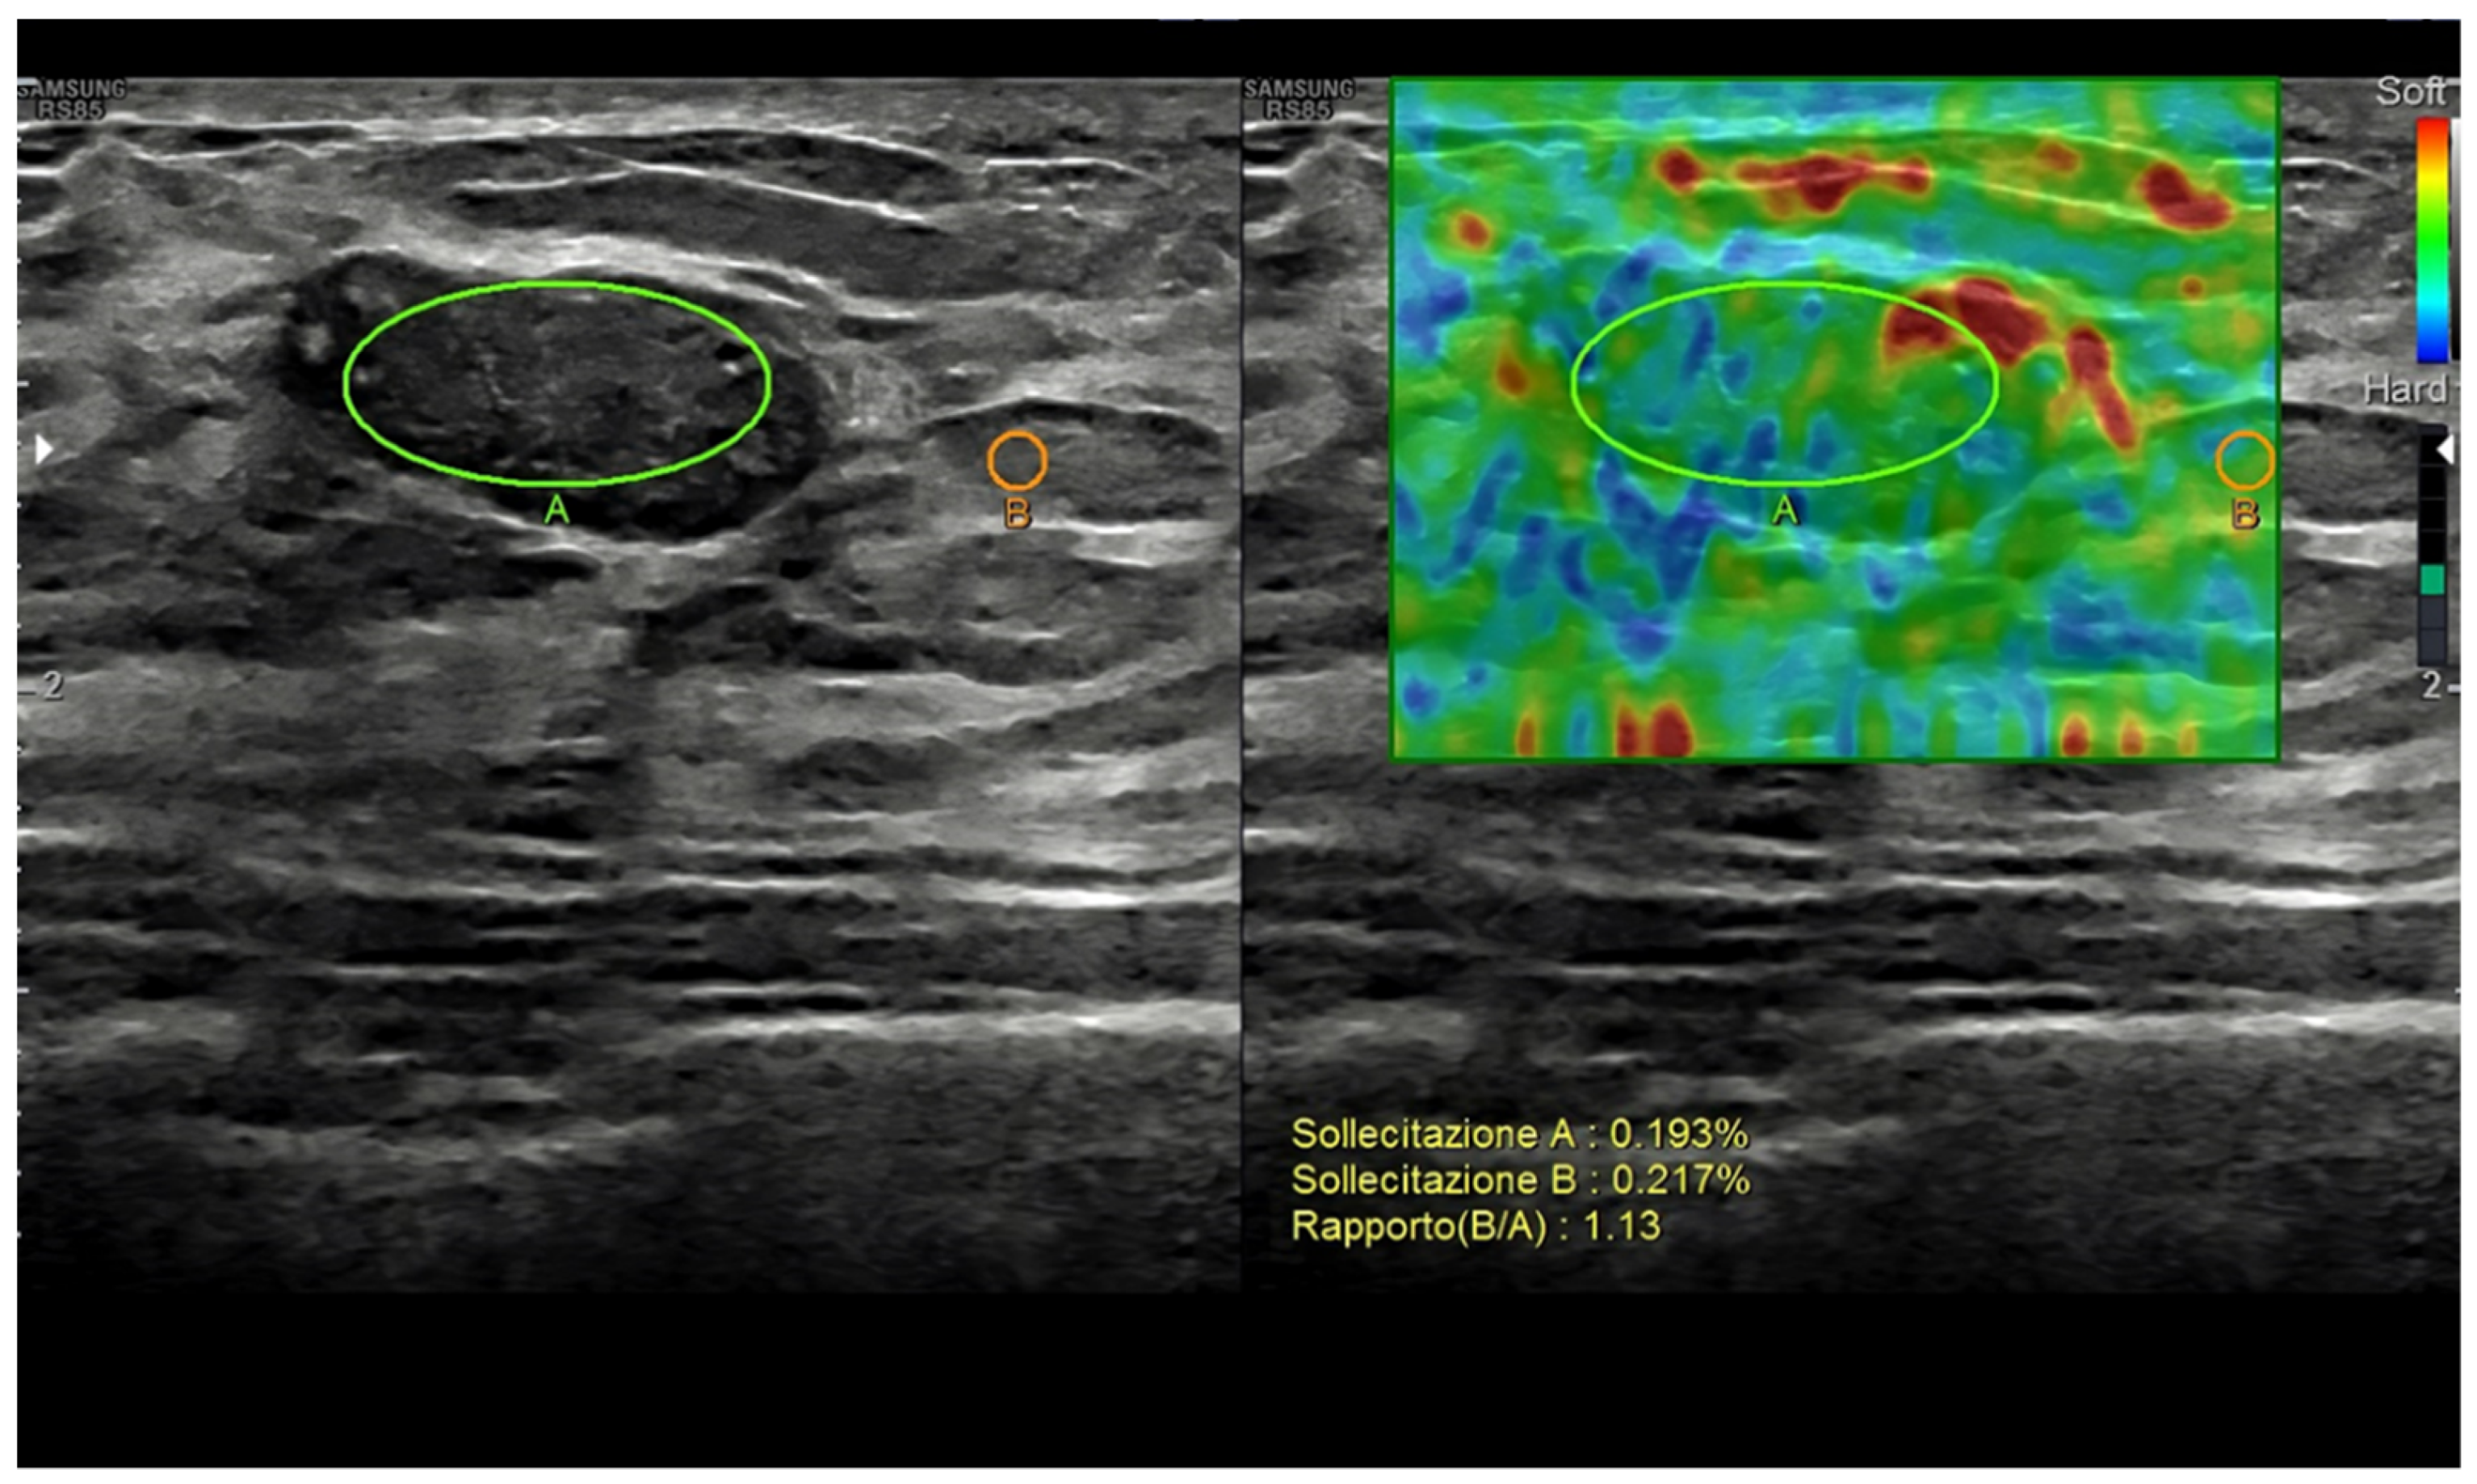

Figure 4. Breast fibroadenoma. Strain ratio allows a semi-quantitative assessment of the lesion-to-fat stiffness.

US elastography measures small tissue motions due to pressure forces, i.e., the viscoelastic properties of breast abnormalities [40]. Current techniques include strain elastography, based on the manual pressure from the operator; acoustic radiation force impulse imaging (ARFI); point shear-wave elastography; and 2D/3D shear-wave elastography, based on the changes provoked from the focused ultrasounds themselves. Based on the different techniques, qualitative (subjective scoring), semi-quantitative (strain-to-fat ratio), and/or quantitative data can be obtained [7,8,37,41,42,43,44,45,46,47,48,49].

The use of elastography has been mostly focused on breast nodule characterization, but aspects such as tumor detection, tumor extent assessment, axillary lymph node status, percutaneous procedure guidance, and tumor response to treatment assessment must also be considered [41,50,51,52]. As a general rule, stiffer nodules (i.e., score 1 or 2, low strain ratio, low shear-wave speed), opposing a significant resistance to the changes, are thought to be malignant, while elastic ones (i.e., score 4 or 5, high strain ratio, high shear-wave speed) are usually categorized as benign [53] (Figure 4).